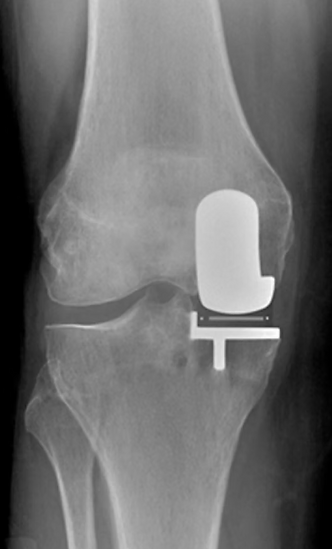

X-Ray of a dislocated knee.